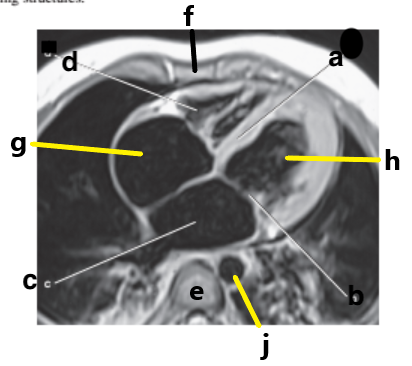

What is letter h ?

Left ventricle

Right ventricle

What is letter f ?

Diaphragm

Clavicle

Ribs

What is letter d ?

What is letter g ?

Right atrium

Descending aorta